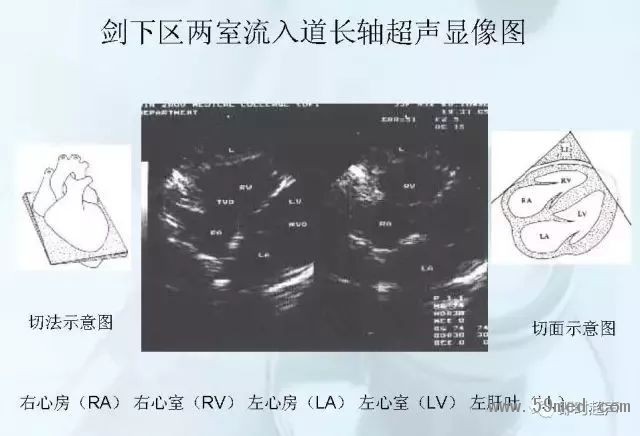

新聞中心 收藏!正常B超解剖圖譜,超實用!